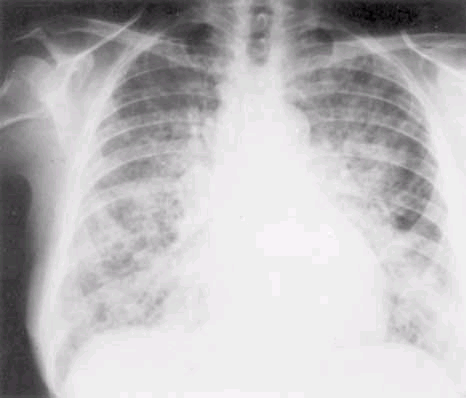

ARDS occurs within 5 days of the initial at-risk diagnosis in the majority of patients, and over 50% will develop ARDS in the first 24 h. The earliest clinical sign is often an increase in the respiratory frequency, followed by dyspnea. There are no characteristic laboratory abnormalities for ARDS patients except those related to a specific underlying condition, such as leukocytosis in sepsis or an elevated serum amylase level in pancreatitis. Radiographically, the lung fields may be clear initially; diffuse bilateral interstitial or alveolar infiltrates occur as ARDS develops (Fig. 265-1). Though these radiographic changes appear homogeneous on chest radiograph, computed tomography demonstrates a heterogeneous pattern with a predominance of infiltrates in the dependent regions of the lung (Fig. 265-2).

Figure 265-1: A standard posteroanterior chest radiograph from a patient

with acute respiratory distress syndrome secondary to a severe viral

pneumonitis. Such a diffuse radiographic change is typical of all conditions

listed in Table 265-2 when they are severe enough to cause acute hypoxemic

respiratory failure. A similar radiographic picture is also seen in pulmonary

edema due to left ventricular failure (Chap. 32).